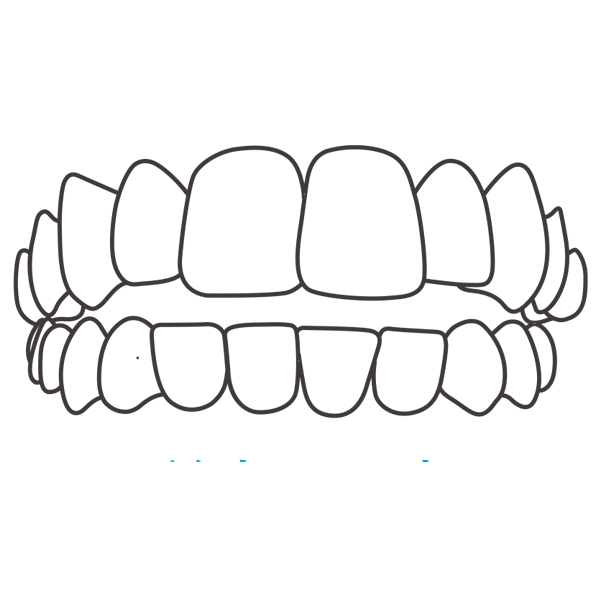

インビザラインGoは、前歯から小臼歯までの歯並びを整える「部分矯正」に特化したマウスピース型矯正治療です。透明なマウスピースを使用するため、目立ちにくく、日常生活に支障をきたしにくいのが特徴です。軽度の歯並びの乱れに対応し、短期間・低価格で理想のスマイルを目指せます。

| デジタル診断 | 光学スキャナーで歯型を採取し、3Dシミュレーションで治療計画を立案。 |

一人ひとりに合わせた歯並びの変化を、3Dシミュレーションでご確認いただけます。